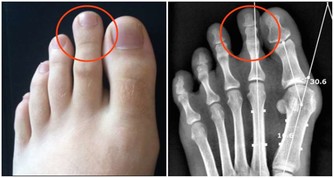

2、痛風

手麻的患者中約有1%是痛風所致,可能因尿酸沉澱在正中神經處,壓迫到正中神經,而出現手麻疼痛問題。